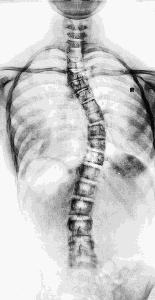

长期使用这样的姿势,会影响到日常正常的体态。当我们正常站立的时候,背部肌群会因为弓背拉伸过度而松弛,很有可能引起「脊柱侧弯」(Scoliosis);

颈部会微微前倾,拍 X 线片子可能会告诉你「颈部曲度变直」;